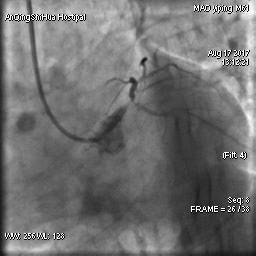

毛先生的血管在心臟左主干體部及分叉部都出現(xiàn)嚴(yán)重狹窄,僅一絲血流通過,前降支的血流已明顯減慢。難怪日常步行都會引起心絞痛,毛先生隨時(shí)都可能心臟驟停。

術(shù)前 心臟左主干末端嚴(yán)重狹窄